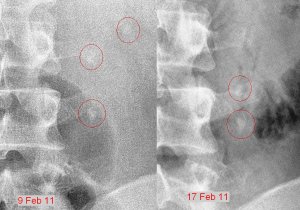

The ultrasound report confirmed the diagnosis. I started treating myself by ingesting potassium citrate mixture 3 times a day to alkalinise my urine. I also had UFEME done regularly to monitor the presence of RBCs in the urine. A week later on 17th Feb, when the RBCs were no longer being detected in the urine, I had another KUB X-ray done.

The KUB on the 17th indicated that the bottom stone was still at the same site but the other two stones has come together and now were on top of each other. But there was no RBCs coming through, so either the bottom stone was blocking everything or the bottom stone had stabilised and was no longer cutting across the surface of my ureter, so no blood in the urine.